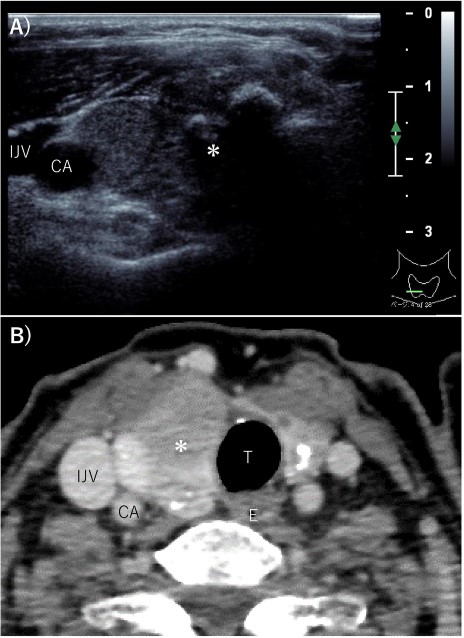

A 70-year-old female without any past medical history underwent total thyroidectomy and central neck dissection for PTC (pT3bN1aM0 pStage II; Fig. 1). Pre-operative blood examination showed a thyroglobulin (Tg) level of 351 ng/mL (normal value of Tg, ≤33.7 ng/mL). After surgery, her Tg level remained around 100 ng/mL (Fig. 2). However, 5 years after initial surgery, her Tg level increased to 366 ng/mL, with subsequent computed tomography (CT) revealing metastasis to the left III (Fig. 3) and right Vb and VI lymph nodes. CT also incidentally observed a right ovarian tumor, for which transvaginal ultrasonography and magnetic resonance imaging (MRI) were performed given suspicions of malignancy (Fig. 4). Blood examination showed a CA125 level of 33.4 U/mL (normal value of CA125, ≤35.0 U/ml). Given suspicions of malignancy by our hospital’s department of gynecology, total hysterectomy and bilateral adnexal resection had been conducted. A pathological diagnosis of OG with no malignancy was then established (Fig. 5). The patient’s post-operative Tg level decreased to 143 ng/mL (Fig. 2). For lymph node metastasis of PTC, right neck dissection and left III lymph node resection by sternal incision were performed. The left recurrent laryngeal nerve was resected due to the invasion of the left III lymph node. Though post-operative swallowing rehabilitation was needed, she was discharged 9 days after surgery with good clinical course. Post-operative blood examination showed a significant decrease in the Tg level (5.9 ng/mL).

Pre-operative imaging findings of papillary thyroid cancer. (A) Ultrasonography revealed a hypoechoic 28-mm mass with internal calcification was found in the right lobe of the thyroid gland. (B) Contrast-enhanced CT revealed a 37 mm× 25 mm tumor in the right lobe of the thyroid gland without surrounding invasion and no lymph node metastasis or distant metastasis. *: tumor, CA: carotid artery, IJV: internal jugular vein, T: trachea, E: esophagus.